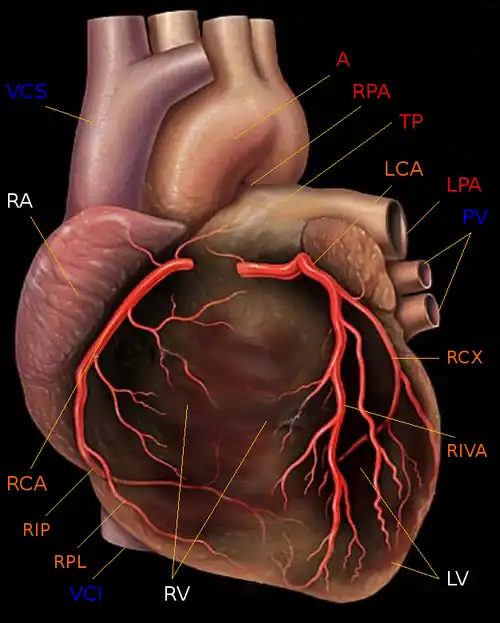

– Herzkammern und -vorhöfe (weiß): rechter Ventrikel (RV), rechter Vorhof (RA) und linker Ventrikel (LV).

Der linke Vorhof (LA) wird durch den linken Ventrikel verdeckt.

– Arterien (rot) und Venen (blau) des großen und kleinen Kreislaufs: Aortenbogen der Aorta (A), Truncus pulmonalis (TP) mit linker und rechter Pulmonalarterie (RPA und LPA) sowie Vena cava superior und inferior (VCS und VCI) sowie die linken Pulmonalvenen (PV).

Die rechten Pulmonalvenen sind durch den rechten Ventrikel verdeckt.

– Koronararterien (orange): Hauptstamm der linken Koronararterie (LCA) mit den Hauptästen Ramus circumflexus (RCX) und Ramus interventricularis anterior (RIVA) sowie der Hauptstamm der rechten Koronararterie (RCA) mit den Hauptästen Ramus interventricularis posterior (RIP) und Ramus posterolateralis (RPL).

Der Ursprung der Coronararterien ist in dieser Zeichnung fälschlicherweise an der Wurzel der Pulmonalarterien und nicht im Bereich der Aortenwurzel eingezeichnet!

– Die Koronarvenen sind nicht dargestellt.